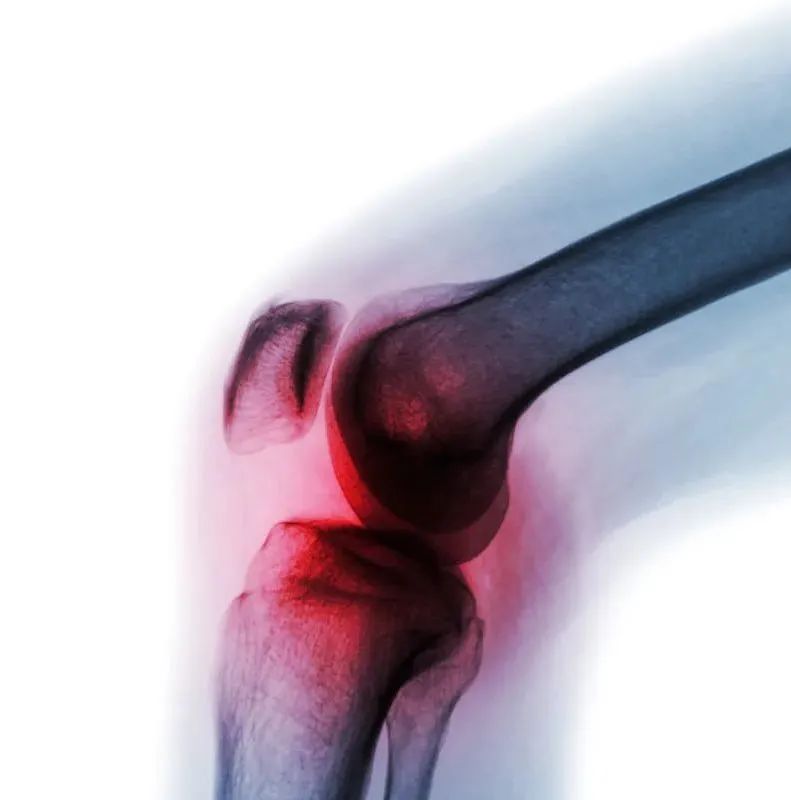

骨關節離我們并不遠

骨關節炎就是一種由于年齡增大、關節勞損、創傷等諸多因素引起的關節軟骨退化、關節骨質增生為特征的退行性病變。不斷增加的發病率以及治療手段有限是目前所面臨的難題。因此,尋求能夠在疾病初期應用的無創性治療手段是當前的目標。